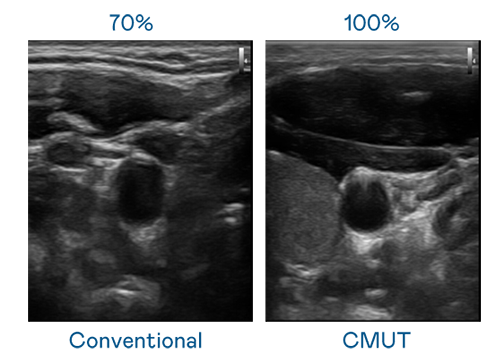

CMUT 技术是一种用电容式微机电元件来产生超音波讯号的技术。与传统 PZT 压电式技术相比,CMUT 频宽增加 30%,更宽频的超音波讯号让影像解析度大幅提升,是实现高影像品质医疗超音波扫描、促进精准医疗发展的关键技术。

大频宽带来超清晰影像

超音波影像的解析度高低,首先取决于探头能发出的讯号频宽。304am永利集团 CMUT 可提供高清晰的超音波讯号,提供高频宽、高灵敏度、影像纹理细节更高的超音波影像,协助医护人员缩短影像判读时间及利用精准的医疗影像进行诊断。